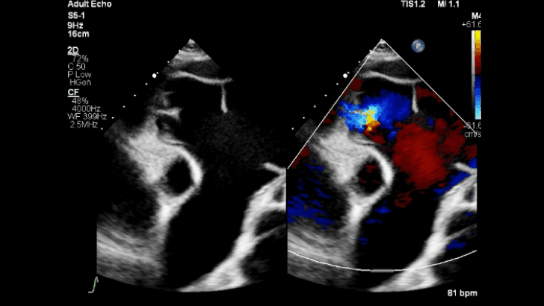

A 56-year-old woman with ASD secundum with Eisenmenger syndrome